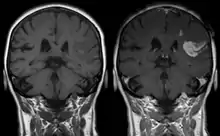

Le gadolinium (sous forme chélatée ou libre) est retenu dans le cerveau, en particulier dans le noyau dentelé et le globus pallidus[11], dès une injection d'un agent de contraste à base de gadolinium (GBCA) (en quantité plus importante pour les linéaires)[12]. Le système glymphatique pourrait être la voie d'accès principale des GBCA au cerveau en intraveineuse[13]. Des études in vitro ont trouvé les agents linéaires (chélateurs moins stables) plus neurotoxiques que ceux macrocycliques[14],[15]. Une étude a trouvé qu'un rehaussement du signal T1 sans administration de contraste (indicateur de la présence de gadolinium) sur les IRM cérébraux d'individus ayant reçu une ou plusieurs injections d'agents linéaires et macrocycliques corrélaient significativement avec une fluence verbale moindre[16]. La confusion est une possible conséquence clinique reportée par plusieurs études[14].